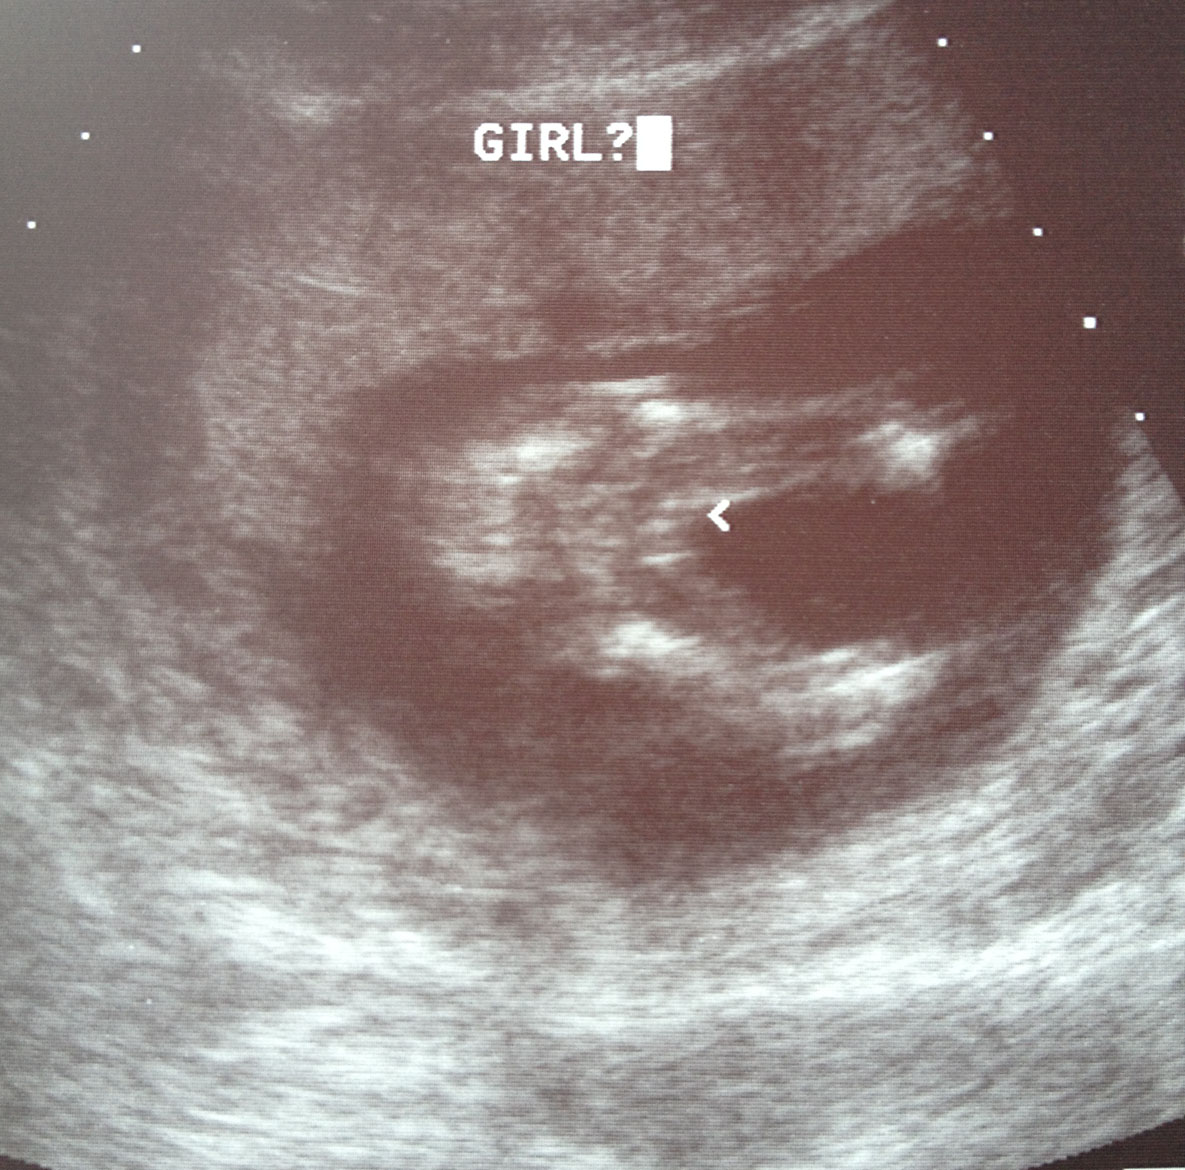

This scan was taken at 16w 3d. At our NT scan (13w) we were given a 70% chance that it was a girl. I go in today for our anatomy scan so hoping that this picture is still the same!!! I was told 3 lines means girl and I am hoping it's true! My son will be a great big brother regardless!